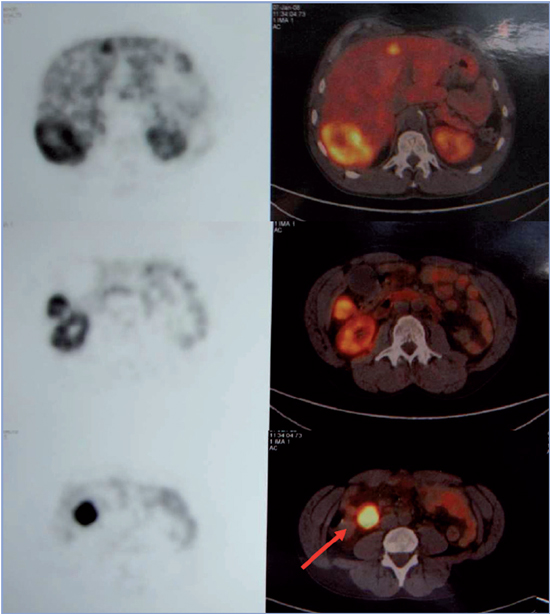

Para la localización del tumor primario y otras posibles localizaciones secundarias se solicitó cintigrama con In111 octeotride-DOTATOC, el que reveló nódulos hepáticos y captación en flanco derecho con receptores activos de somatostatina, y PET-CT Ga-68 DOTATATE que mostró hipercaptación multifocal en hígado e intestino delgado; ambos imágenes eran compatibles con carcinoide de íleon terminal con metástasis hepáticas (Figura 2). La radiografía de tránsito intestinal también ubicó la lesión a nivel del íleon distal.

Figura 2. PET-TC Ga-68 DO-TATATE muestra hipercaptación multifocal en hígado e intestino delgado (flecha) compatible con carcinoide metastásico.

En control ambulatorio efectuado al mes del alta refiere importante regresión de la sintomatología, con 5-HIAA de control de 50 μmol/24 h. Repetido el PET/CT Ga-68 DOTATATE mostró lesión focal hepática hipercaptante en segmento VIII-IVA, compatible con metástasis de tumor neuroendocrino, persistente respecto al estudio inicial. El ecocardiograma no señaló variación respecto al estudio previo. En control clínico a los 2 años el paciente se encuentra estable.